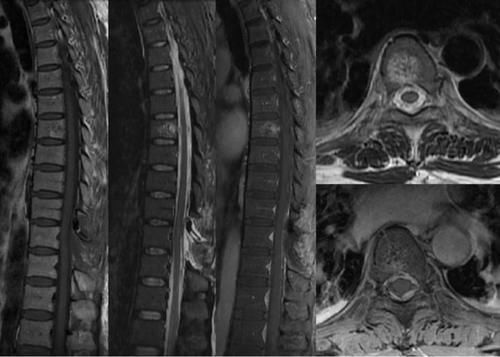

Case10:F,10y;腰痛1月加重2天,无肢体麻木、乏力,无二便障碍 。

文章插图